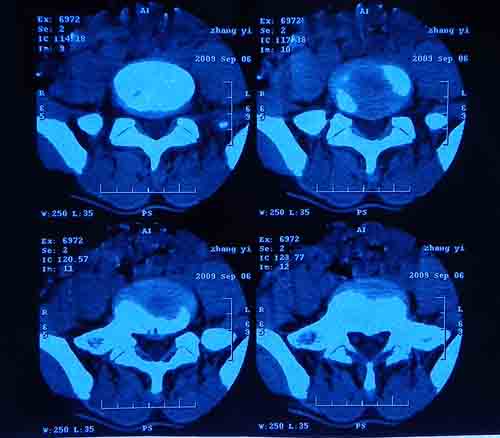

腰5/骶1椎间膨突出外,还有点异常,不知是什么东东,请各位大虾帮忙看看(12骨窗最明显)

椎体后缘软骨结节

软骨结节

支持 椎体后缘软骨结节。